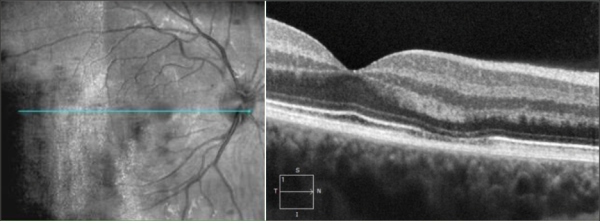

Central Serous Chorioretinopathy (CSCR)

CSCR on OCT shows neurosensory detachment along with clear subretinal fluid often associated with focal serous PED. More recently, enhanced-depth imaging SD-OCT has shown increased subfoveal choroidal thickness in some patients with CSCR, as compared to normal eyes.[25] The outer retinal dipping sign may be noted. Typically, the RPE not involved in serous PED appears straight, unlike inflammatory pathologies, including VKH disease, where the RPE may be undulated.[26]